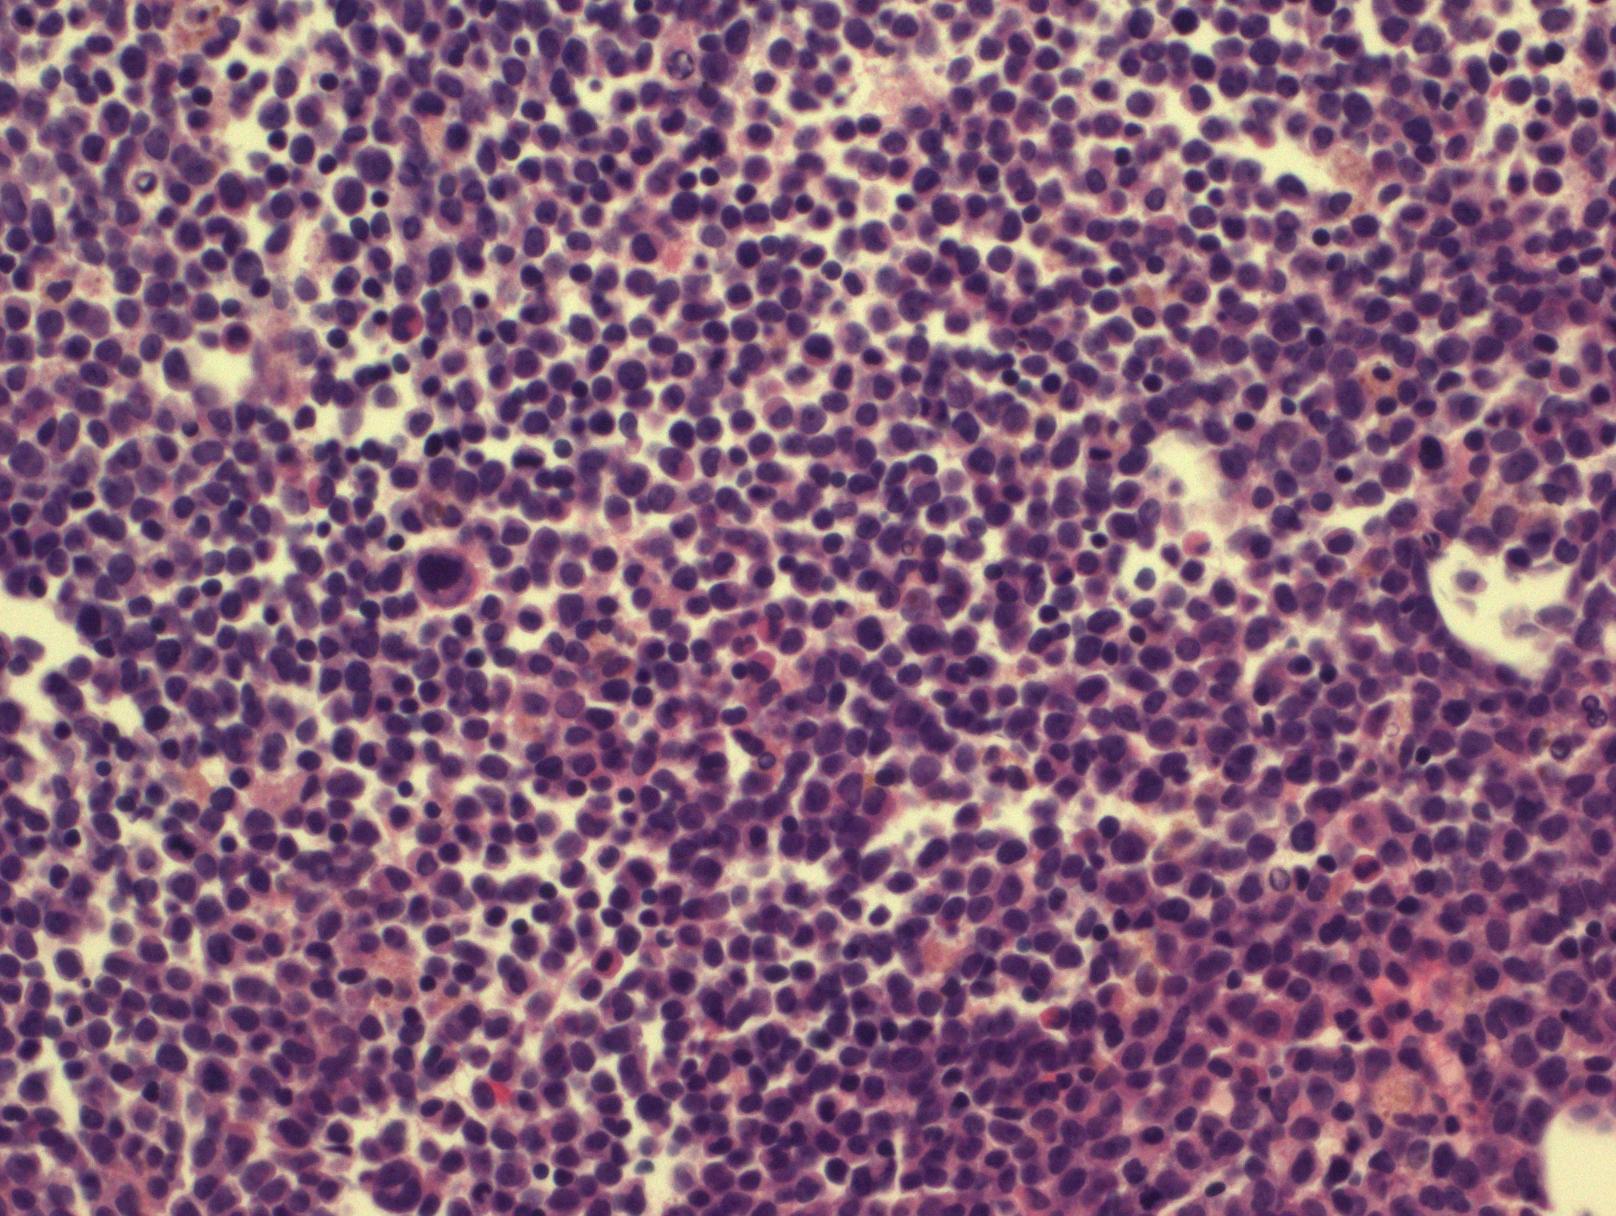

急性粒单细胞白血病

Acute Myelomonocytic Leukemia

急性粒-单核细胞白血病的特征是中性粒系和单核系同时增生,原始细胞(包括原始粒细胞、原单核细胞和幼单核细胞)总和 ≥20%;而所有单核细胞总和(其中包括原单核和幼单核)应 ≥20%,但 <80%(粒系细胞总和至少 20%)。类似于形态学分类的 FAB M4。不满足 AML 伴重现性遗传学异常、AML 伴骨髓增生异常相关改变和治疗相关 AML 的诊断标准。

- 细胞形态学:白血病细胞同时具有粒系和单核分化特征。原始细胞成分包括原始粒细胞、原单核细胞和幼单核细胞,相对成熟成分包括粒细胞和异常单核细胞。原单核细胞核大圆形含显著核仁、胞质丰富噬碱、可有少量散在颗粒,幼单核细胞核轮廓较不规则或有轻微折叠、染色质较疏松、核仁小不明显、胞质含细小颗粒,异常单核细胞核明显不规则和折叠、染色质较致密、胞质含颗粒较多。

- 骨髓原始细胞(原始粒细胞、原单核细胞和幼单核细胞) 总和 ≥20%,单核系细胞总和 ≥20% (但 <80%),粒系细胞总和 ≥20%。联合 CAE 和 NSE 染色可帮助识别粒和单核成分。